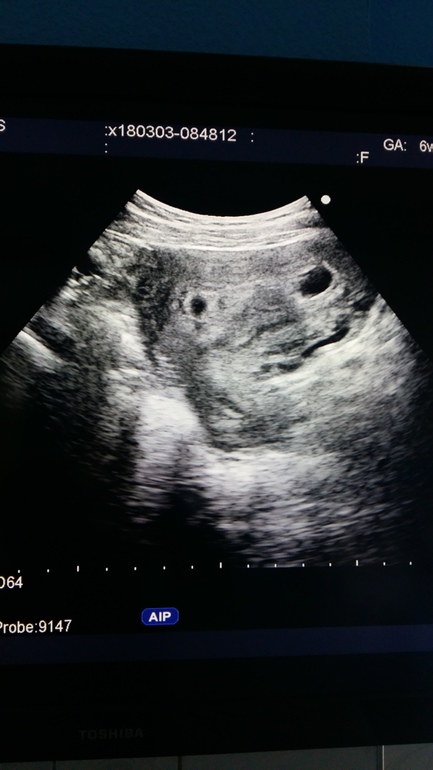

это двойня... если я правильно пончла... поосто второе плодное яйцо поменьше.. я думаю, что все будет хорошо к 12 неделям сравняются)

Было с первой беременностью, на первом узи показало - один дорос до 6мм и сердцебиение было, второй до 1мм. Врач меня сразу успокоила, сказала скорее всего рассосётся, что это закон природы, выживает сильнейший и на второй плод это никак не влияет. Через 2 недели маленький был еле заметен, а не скрининге в 12 недель и вовсе никто не заметил. Сыну 9 лет, все хорошо. Оказывается у двух подруг такое было, так что довольно часто бывает.

6 недель и 5 дней по М

Сказала контрольное УЗИ через неделю...возможно 2 плодых яйца 1 оплодотворилось, а втрое нет...а можно быть отслойка...толком ничего не сказали, хотели положить..отказалась..назначили лечение, ждём неделю.

Под вопросом пока((( динамика через неделю...возможно второе плодное яйцо, но пустое. возможно будет расти и окажется не пустым, а может отслойка и просто выйдет...не понятно пока, но мне уже страшно(